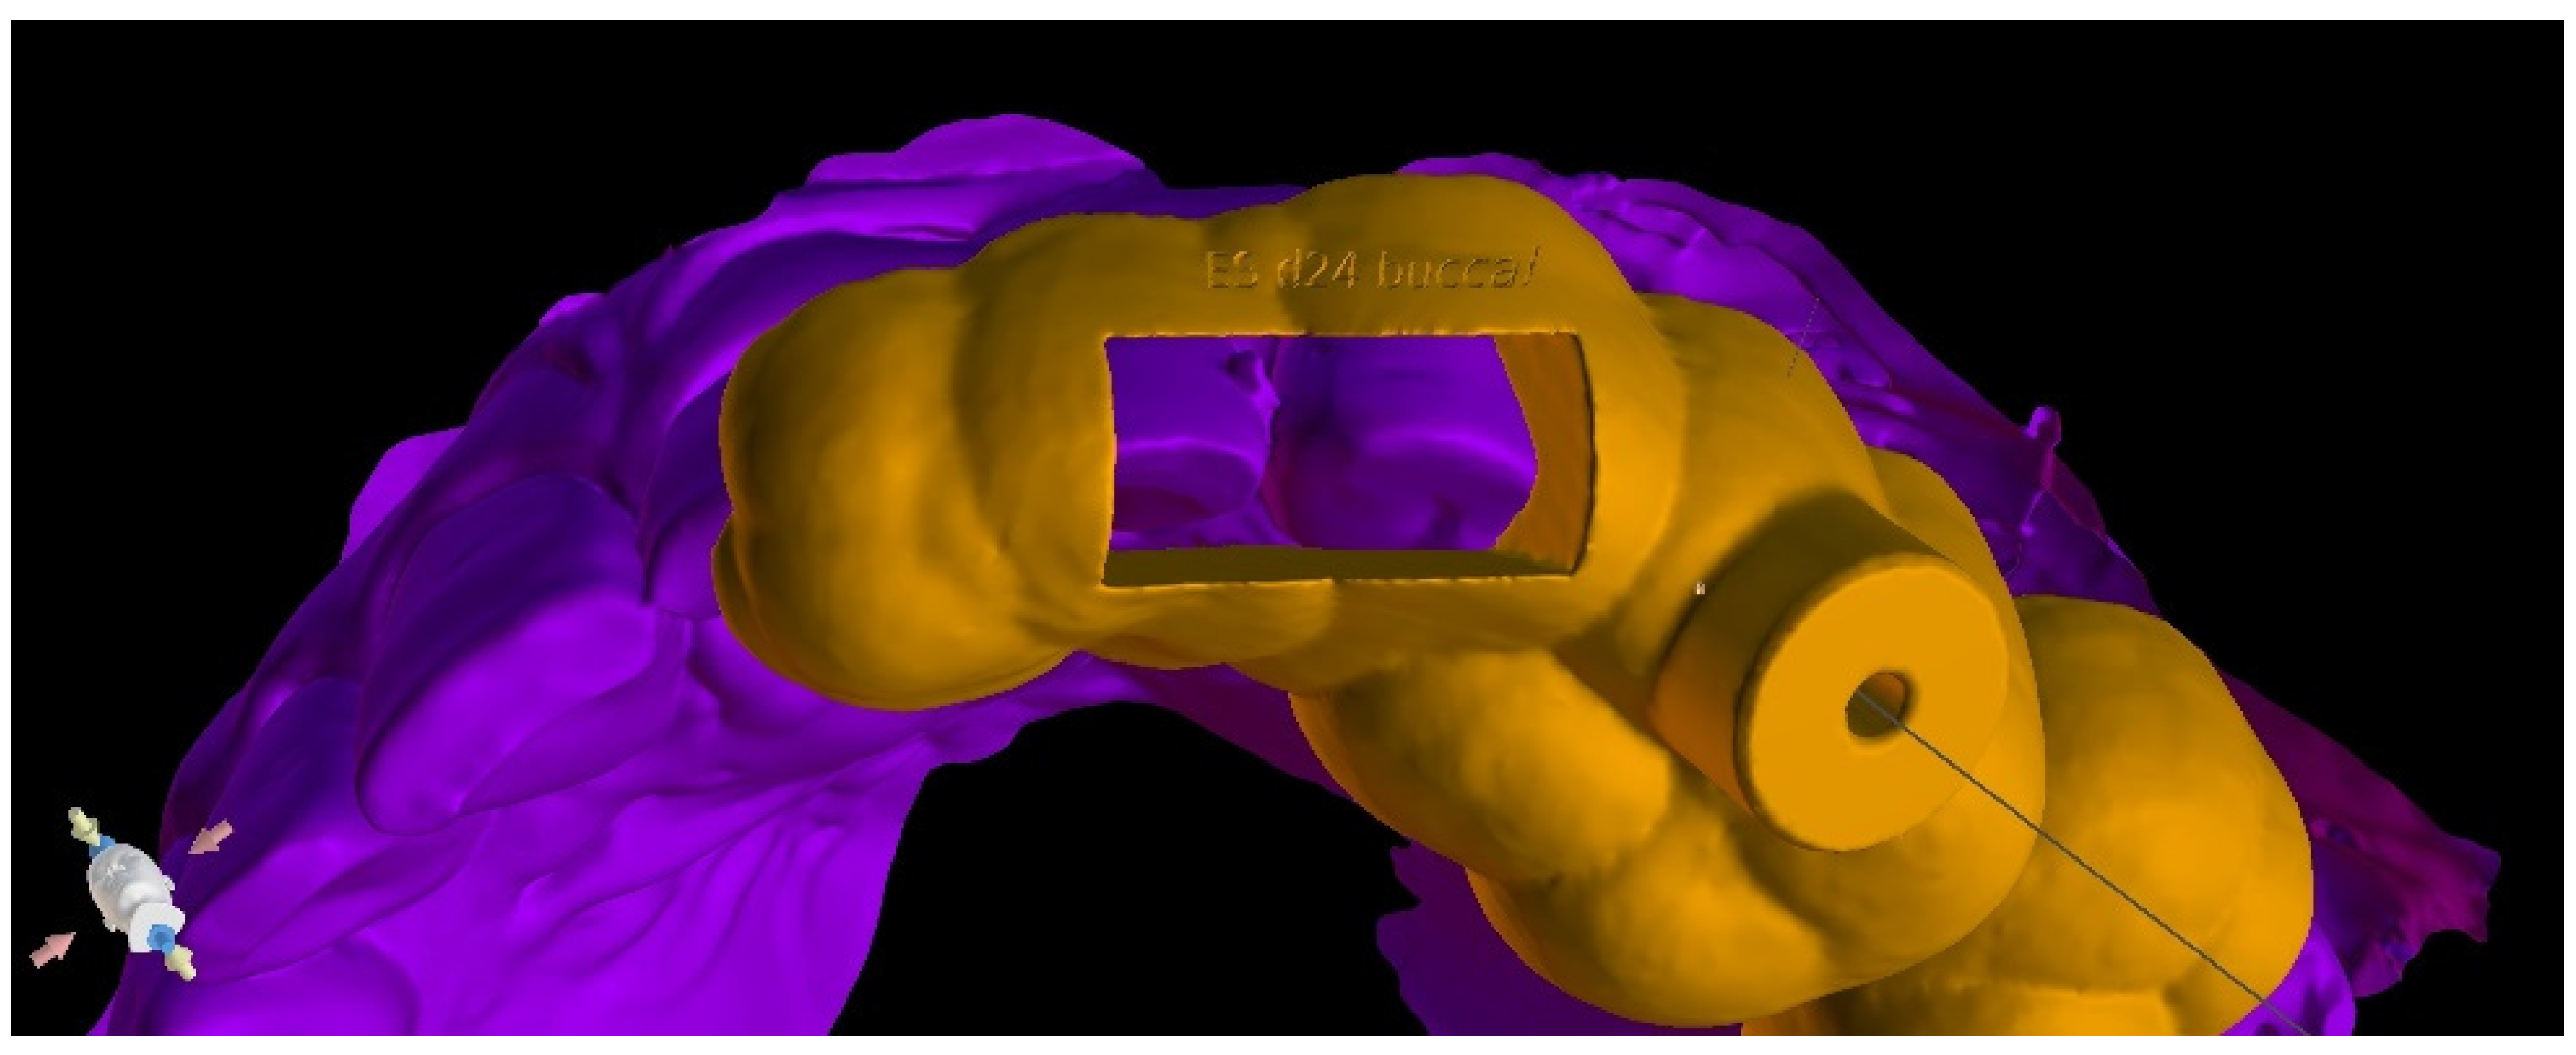

The guided endodontics demanded more complex planning in this case due to artefacts caused by metal restoration in a neighbouring tooth (the second premolar, tooth 25) and the completely nonvisible root canal. According to Buchgreitz et al., when CBCT does not allow clinicians to visualize the canal, the target point in single-rooted teeth can be established through the centre of the root, as seen in the axial view [25]. Despite the fact that tooth 24 is not a single-rooted tooth, in this case, the virtual drill orientation was defined through the centre of the buccal root. A margin of 2 mm to ensure sufficient root dentine thickness was preserved, as there was no visible part of the root canal. The top of the sleeve was 15.5 mm from the bottom of the tooth chamber. The guide sleeve was 6.5 mm long and 1 mm in diameter (Figure 20). The teeth-supported guide was designed with an embossed canal marking (Figure 21).

Figure 20. CBCT image presenting (a) virtual implant positioned through the centre of the buccal root, preserving a safe amount of the tooth’s hard tissues; (b) guide tube designed to reach the bottom of the chamber after 15.5 mm. In the lateral dentition area, short guide tubes may ensure more space for the drill.

Figure 21. Three-dimensional image of (a) endodontic guide range and (b) embossed canal marking on the labial template’s surface.

As in the previous case, the virtual drill orientation was established in the centre of the root. The top of the sleeve was 14 mm from the bottom of the tooth chamber. The guide sleeve was 6 mm long and 1 mm in diameter (Figure 26). The template with engraved canal markings was equipped with a window for assessing the correctness of the guide’s intraoral placement (Figure 27). The buccal canal was cautiously negotiated through the guide with a size 10 file (C-Pilot #10) instead of rotated burs. The root canal orifice was reached at a length of 15 mm from the top of the guide sleeve. The time needed to localize the canal path in this case was approximately 10 min. The file was taken to the working length and a conventional root canal treatment followed (Figure 28).